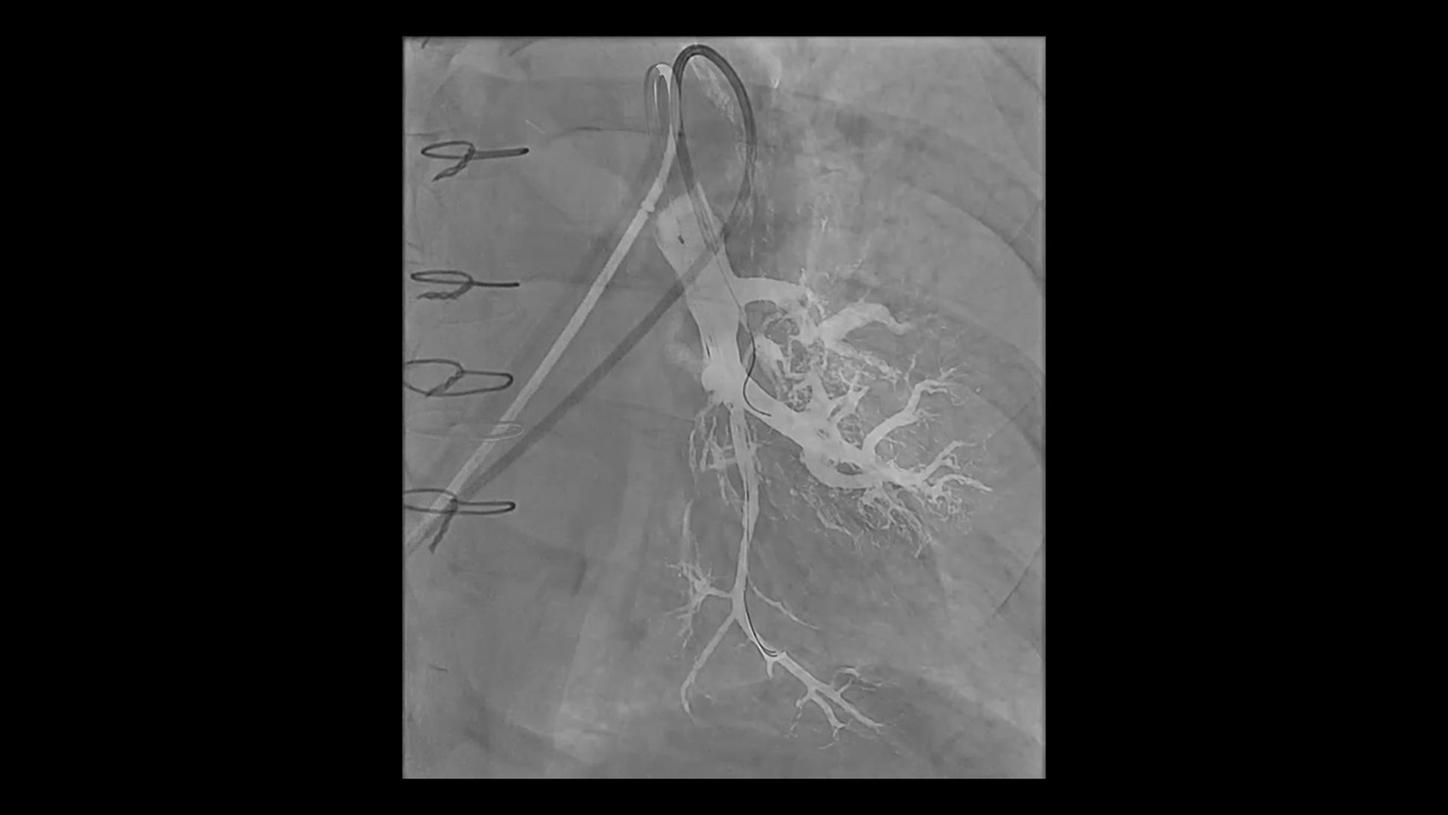

Discover how leading clinicians are transforming interventional radiology with Siemens Healthineers technologies. From ultra-fast 3D imaging to laser-guided needle procedures, the ARTIS icono ceiling powered by OPTIQ and syngo DynaCT are redefining what’s possible in IR. Explore real-world cases, expert insights, and the future of image-guided therapy.